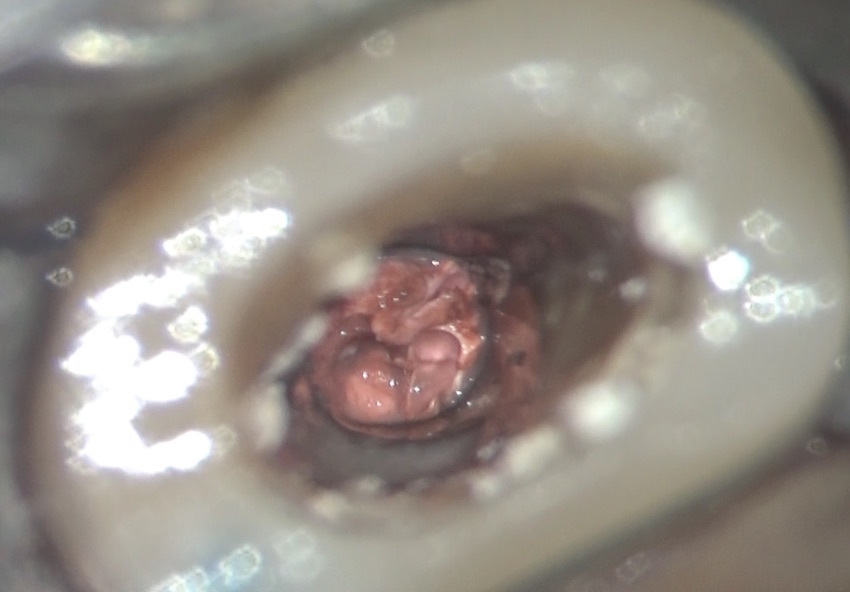

実際に内部の状況を見てみると・・・

こんなに汚れています。今回のケースでは、綿が入っていました。

その綿を取り除くと、一般的に使用するガッタパーチャポイントが入っていて、その周囲には炎症性の体液と思われる液体が存在していました。